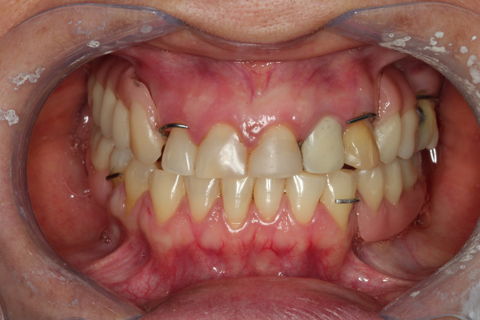

Oclusão PPR´s Iniciais

Paciente chegou no consultório relatando incomodo no elemnto 13, ao executar os exames clínicos e radiográficos constatou-se uma trinca na raiz, gerando a mobilidade e instabilidade da coroa e do pino metálico, foi então feita a exodontia do mesmo. Também constatou-se mobilidae acentuada no elemento 35 necessitando também da exodontia. Foi feita 2 PPR´s provísorias, uma superior e uma inferior, pois a paciente já apresentava PPR´s ao início do tratamento e essas após a exo não apresentam retenção.Segue imagem das PPR´s provisórias, esperando a correta cicatrização e adequação do meio bem como restaurações necessárias, para confecção das próteses definitivas.